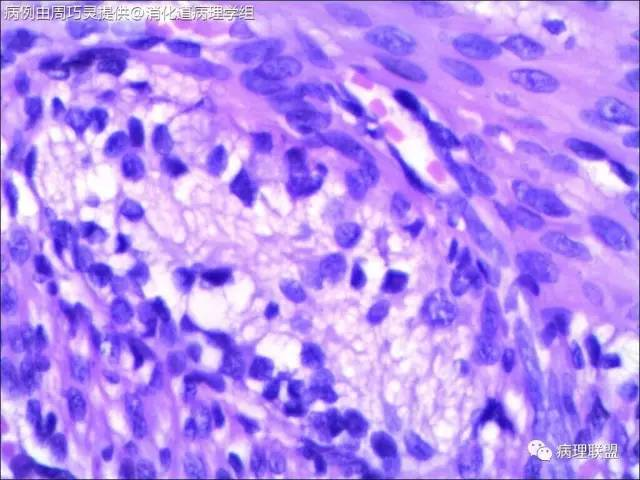

引产胎儿,小肠扩张,肠管回盲部以下直径<回盲部以上。取回盲部及升结肠肠壁镜检。(病例由周巧灵提供,致谢!)

请教各位老师,这些神经节是否正常?是先天性巨结肠吗?正常胎儿的神经节细胞也是核大核仁大的细胞吗?

@石雪迎 石老师,取的就是扩张肠管远端狭窄处,刚好就是回盲部。我在肠壁中见到比较多的神经节,但是里面很少见正常成熟的神经节细胞,应该是支持巨结肠的。不过,我不知道,胎儿时期肠壁正常的神经节是啥样子,所以,不太敢确定,还请老师指点。

这是我在图片中仅见的几个节细胞

@周巧灵 抱歉看错了,以为是结肠扩张。不知道是多大周数引产的胎儿?理论上4个月的胎儿肠神经丛就完成从近端到远端的分布,但直到出生,神经节里的都有不成熟的节细胞。您的图片里确实大部分都没有成熟神经元,但有的似乎不能排除有不成熟神经元,可以染NSE看看,如果还有,诊断HD就没有依据了。中华病理杂志曾经发表过何乐健教授等写的一篇HD病理诊断规范,尤其是有关取材的建议很实用,不妨参考一下